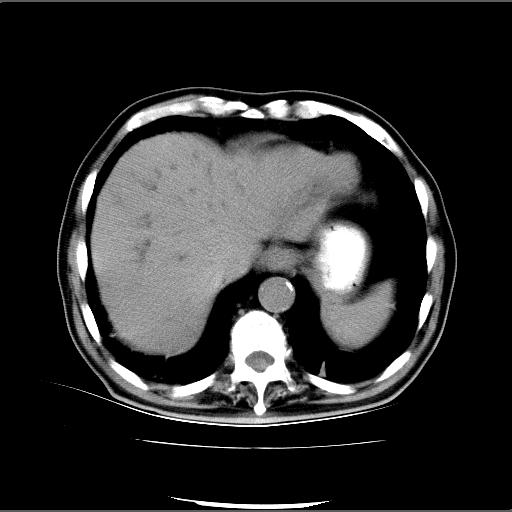

患者男82岁,黄染,发热10天,无腹痛。

1胆总管下端结石伴肝内外胆管扩张;2胆囊颈部结石伴胆囊积液

胆囊多发结石,胆囊积液;胆总管中下段结石,中上段扩张。

胆总管下段结石伴胆道系统扩张;胆囊炎伴胆囊结石.

1、胆总管壶腹部结石并胆总管、胆囊及肝内胆管扩张。2、胆囊多发结石。3、两下胸膜局限性增厚。4、胃体部大弯侧胃壁稍厚,建议:多量饮水后增强ct扫描除外占位性病变。

此病例有结果了:患者术后为:胆总管下段结石伴胆道系统扩张;胆囊炎伴胆囊结石。

各位战友分析的都很正确,是一个典型的病例。